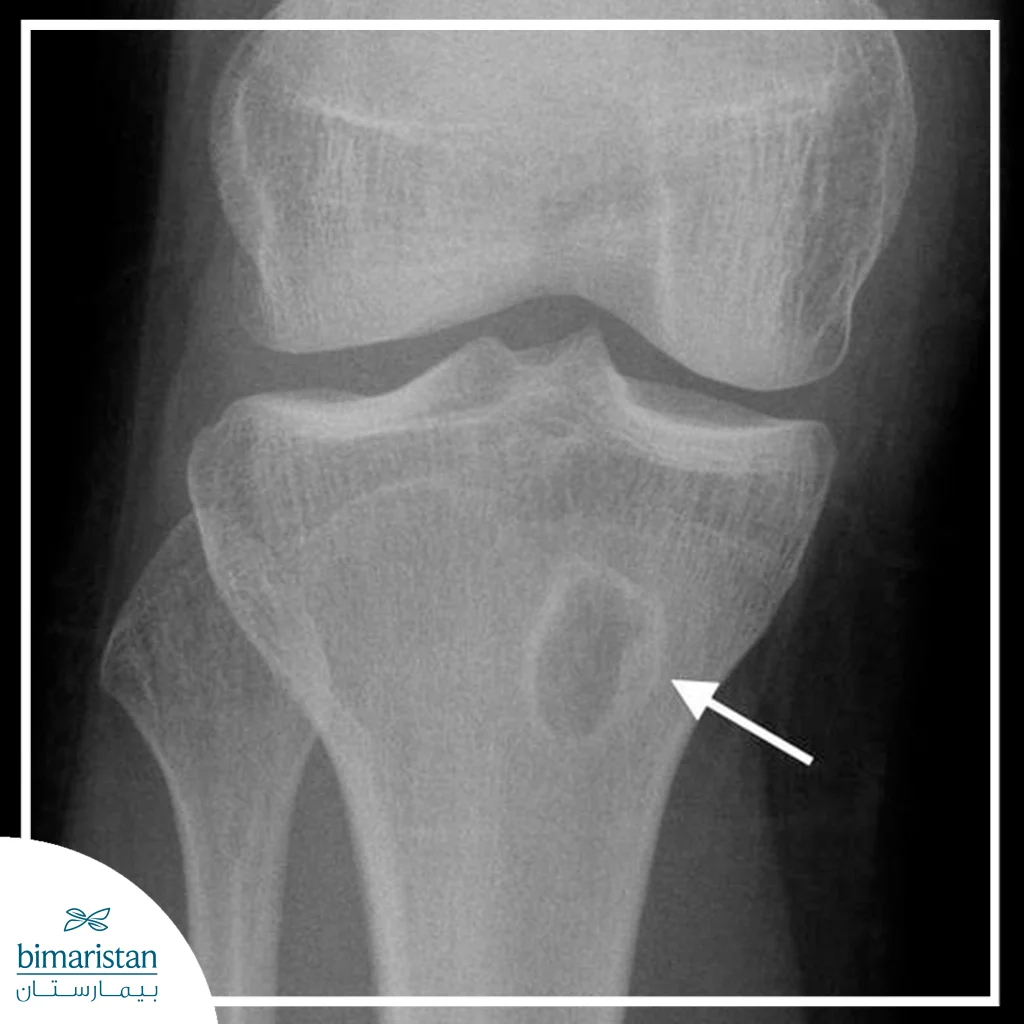

التصوير بالأشعة السينية

إنّ الأشعة السينية هي صورة أولية تُظهر تآكلات أو فراغات عظمية أو تشكّل أجزاء ميتة للعظم في المراحل المتأخرة لكنها قد تكون طبيعية في المراحل المبكرة لأن التغيرات العظمية الظاهرة تحتاج أسابيع لتظهر، لذا تُستخدم كخط أساس ثم تُكمل بصور أو طرق أشد حساسية إذا كان الاشتباه مبكراً.